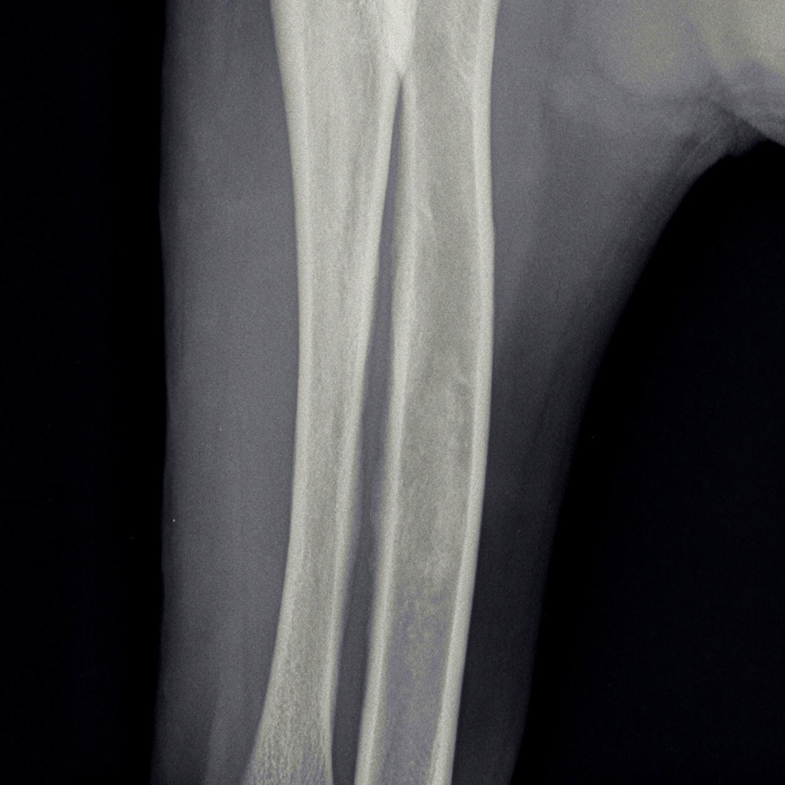

Op röntgenfoto’s kan groeipijn vaak zichtbaar gemaakt worden; het uit zich als wolkvorming in de mergholtes van de lange botten. De pijnlijkheid kan meestal met pijnstilling opgelost worden. Omdat het echter alle lange botten kan aantasten, wisselt de kreupelheid die hiermee gepaard gaat regelmatig van poot. Het kan dan ook voorkomen dat de kreupelheid in bijvoorbeeld de voorpoot overgaat, om na een maand in de achterpoot op te treden.